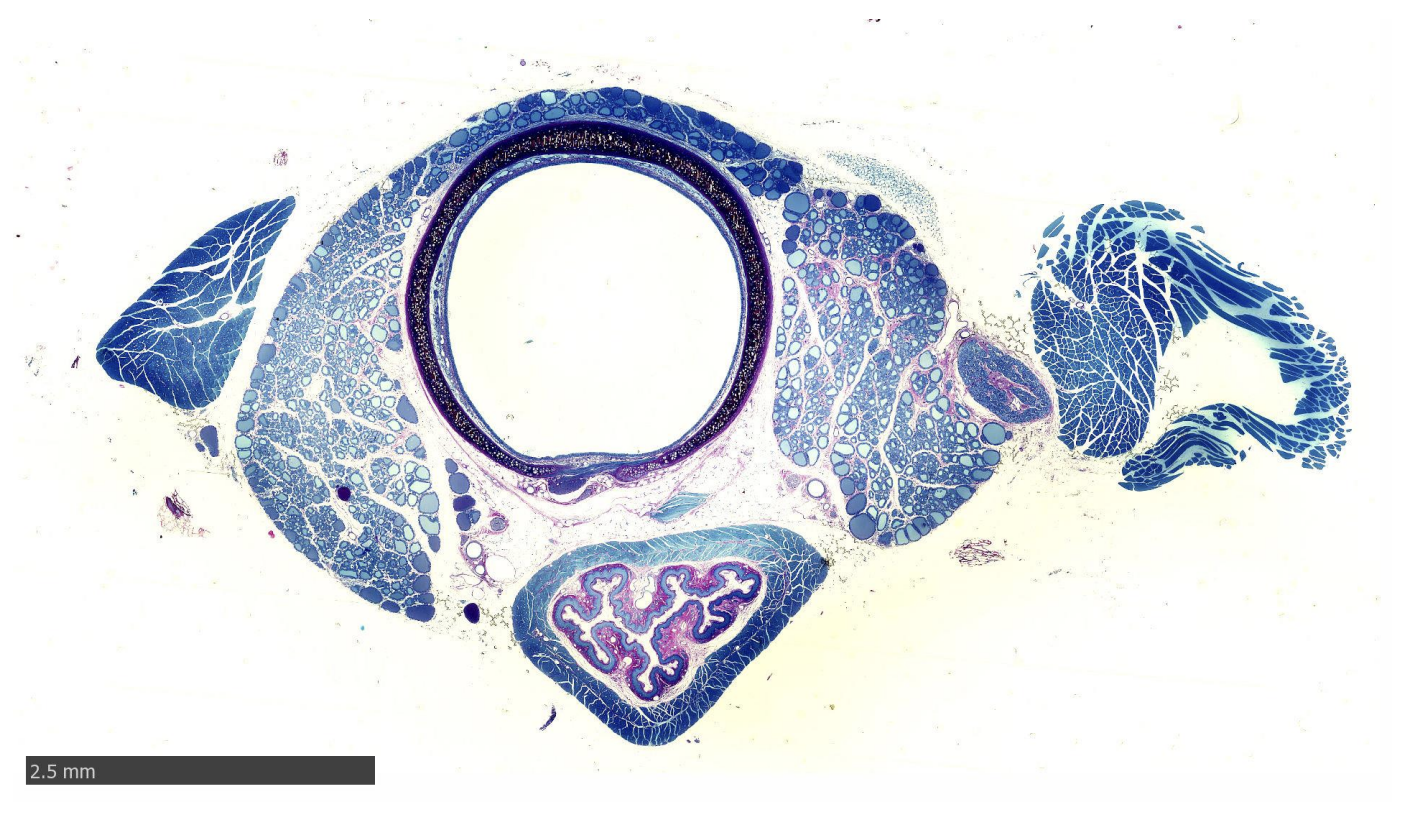

Oesophagus and Trachea of rat

Epithlia?

epithelia?